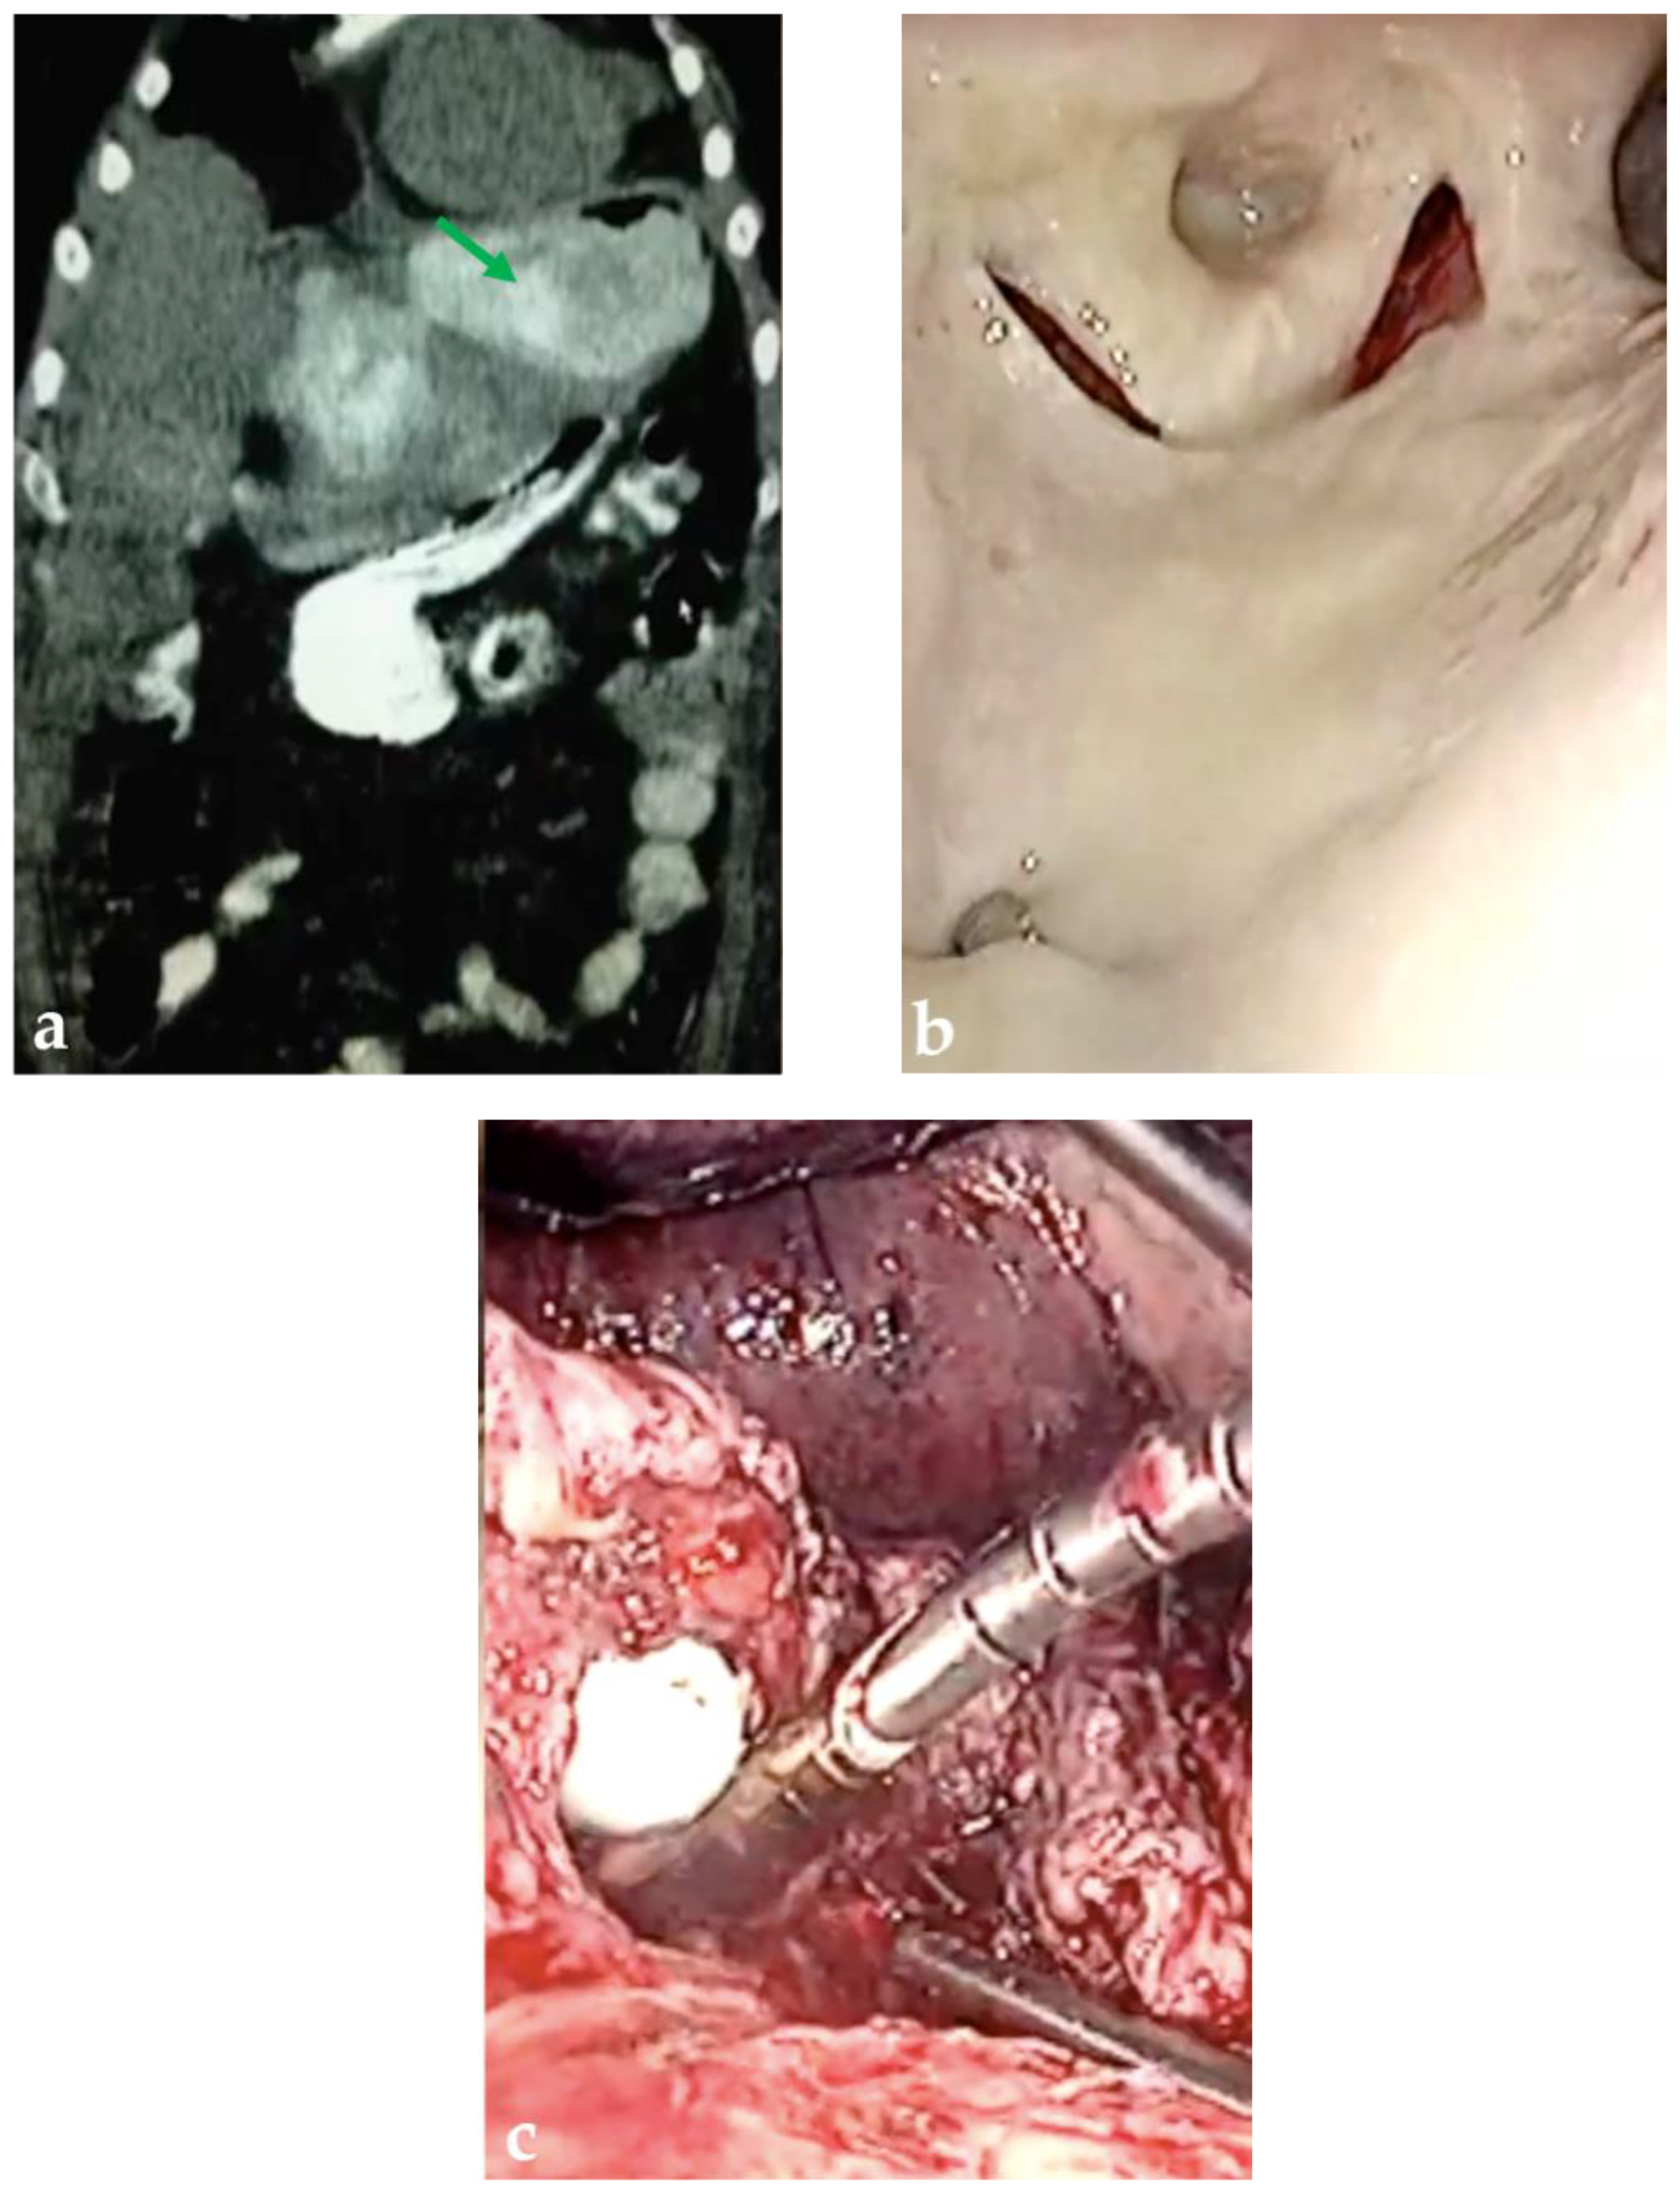

Successful Management of Gastric Leakage Post Gastric Sleeve by Gastric Bypass Conversion

2. Detailed Case Description